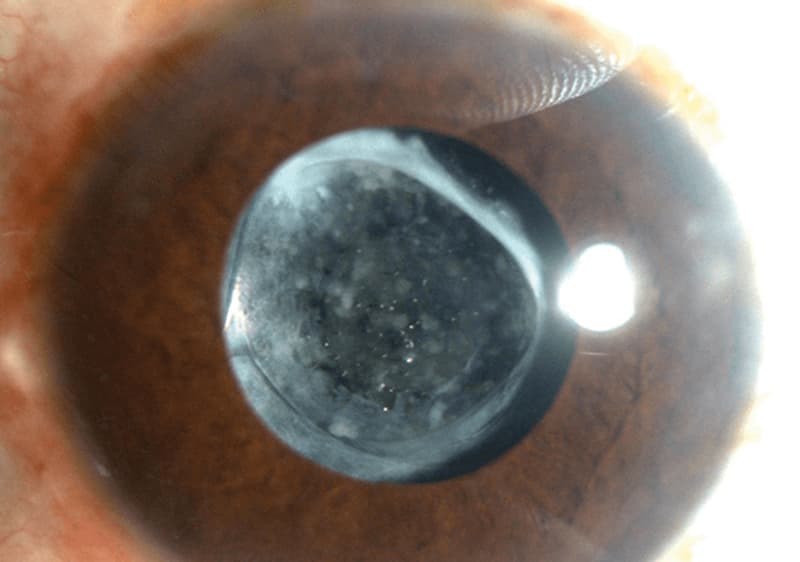

Cirugía de catarata con implante ocular

Remoción del cristalino opaco y sustitución por un lente artificial.